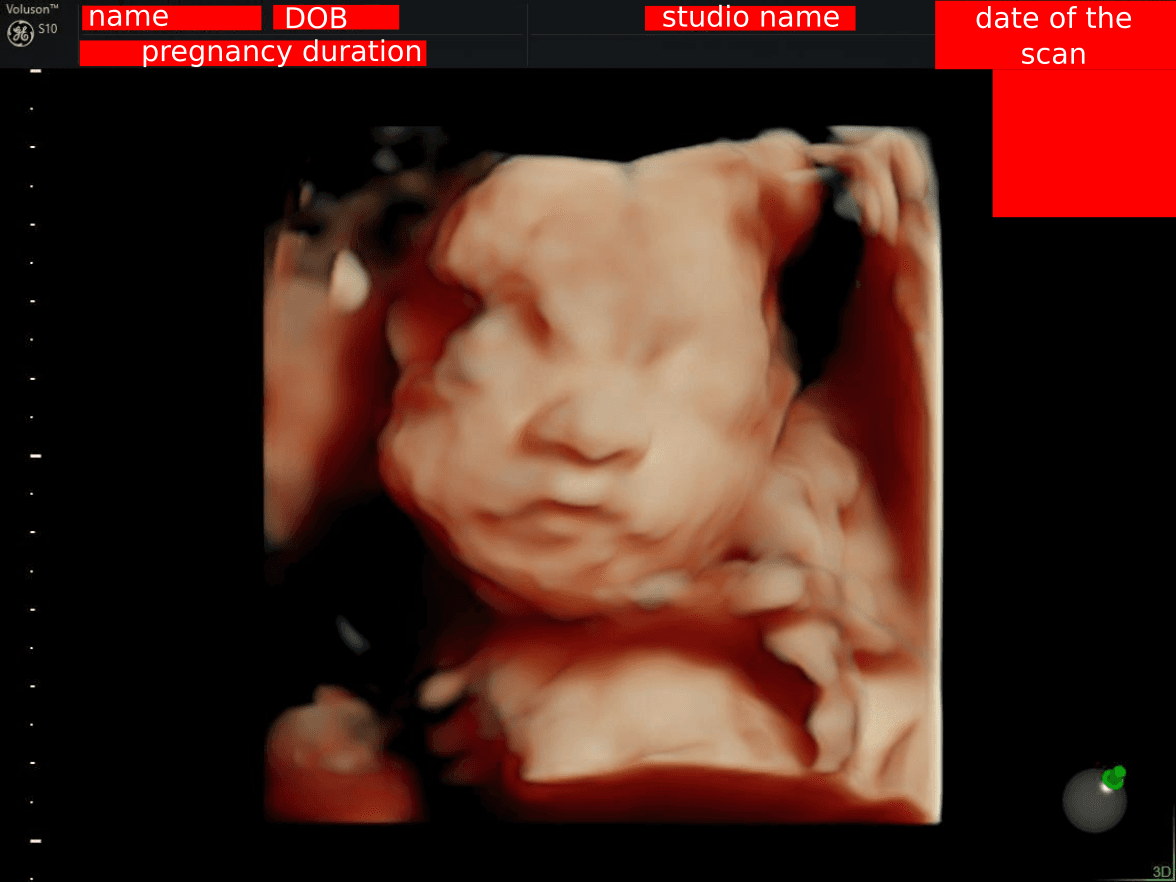

When you get a 3D ultrasound, you often receive a screenshot of the ultrasound machine's screen, like this:

This image includes:

- Your name

- Date of birth

- Pregnancy duration

- Studio name (which can hint at your location)

- Date & time of the scan

Sharing the full image can be risky due to identity theft concerns.